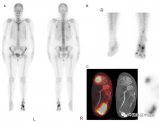

uEXPLORER助力南方医科大学南方医院核医学科在FAP显像方面取得多项成果

近日,南方医科大学南方医院核医学科在科室负责人唐刚华教授带领下,在新型靶向成纤维细胞活化蛋白(FAP)PET分子探针临床转化方面取得了重要进展,相关研究成果分别发表在影像医学与核医学国际顶级期刊European Journal Of Nuclear Medicine and Molecular Imaging (2篇,中科院1区,2021年IF = 10.057)和Radiology(1篇,中科院1区,2021年IF = 29.146),药学顶级期刊Acta Pharmaceutica Sinica B。 2022-06-30 PET/CT